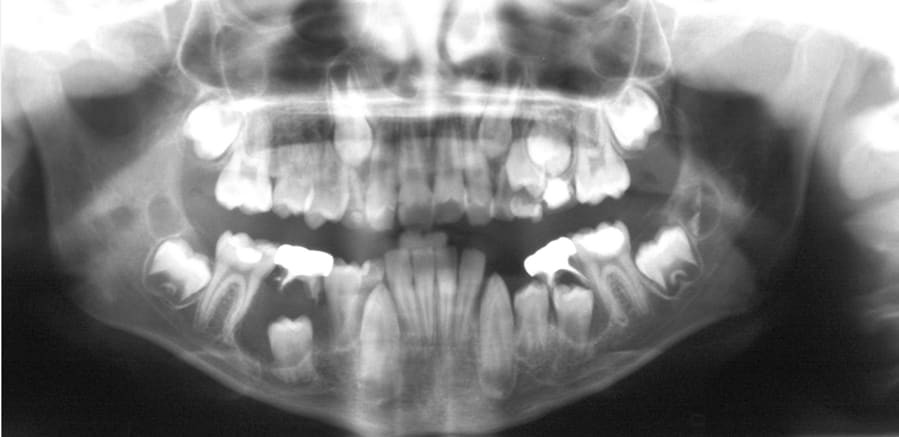

Dentigerous cysts are the second most common type of odontogenic cyst, which is a fluid-filled sac that develops in the jaw bone and soft tissue. They form over the top of an unerupted tooth, or partially erupted tooth, usually one of your molars or canines. While dentigerous cysts are benign, they can lead to complications, such as infection, if left untreated.

How is it diagnosed?

Small dentigerous cysts often go unnoticed until you have a dental X-ray. If your dentist notices an unusual spot on your dental X-ray, they may use a CT scan or MRI scan to make sure it’s not another type of cyst, such as a periapical cyst or an aneurysmal bone cyst.